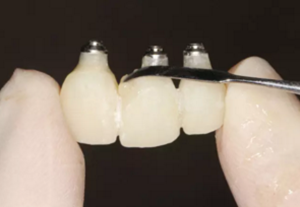

圖22 最終修復(fù)體

圖23 最終修復(fù)后即刻口內(nèi)像

(4)最終修復(fù)。種植體周圍軟組織改建成熟以后,進行最終修復(fù)。本 病例采用兩步法印模技術(shù)精確記錄種植體的三維位置和種植體周圍軟組織穿 齦輪廓外形。 首先,口內(nèi)制取臨時冠及周圍軟硬組織的硅橡膠陰模,復(fù)制軟硬組織 表面形態(tài)。然后,取下臨時修復(fù)體,常規(guī)制取閉窗式種植體水平聚醚印模, 精確記錄種植體的三維位置,灌制含人工牙齦的超硬石膏模型。最后,去除 模型上的人工牙齦,將臨時修復(fù)體戴入到模型上,在臨時修復(fù)體周圍和硅橡 膠陰模內(nèi)注入人工牙齦,將陰模就位到含臨時冠的石膏模型上,精確轉(zhuǎn)移穿齦輪廓外形,獲得工作模型。 制作螺絲固位的一體化氧化鋯基臺冠,以切削方式制作完成后,表面 添加飾瓷來獲得理想的美觀效果。 術(shù)后7個月,戴入最終修復(fù)體,紅白美學(xué)效果滿意。